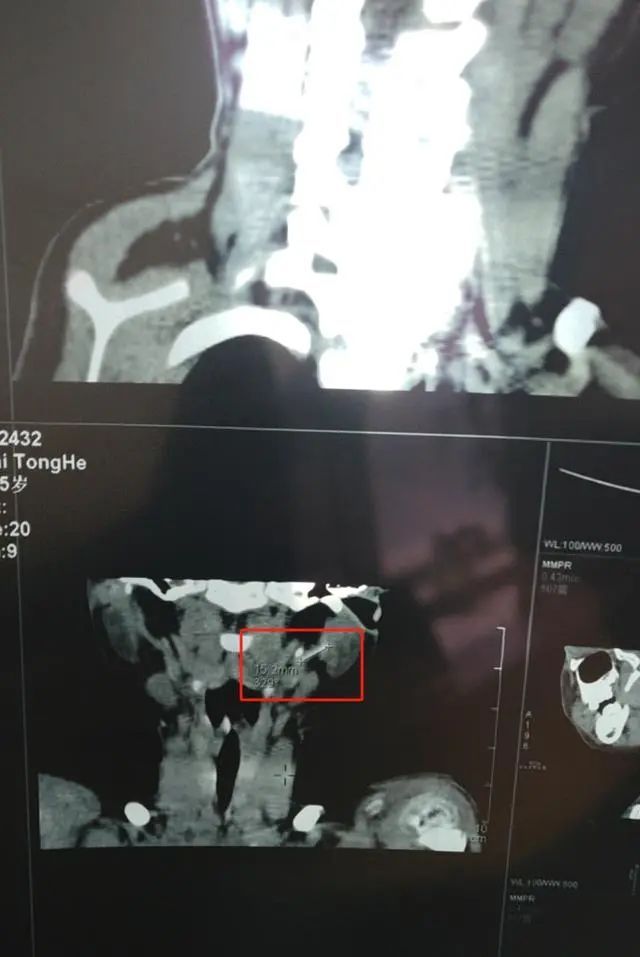

直到2023年10月,白先生带儿子去首都医科大学附属北京儿童医院体检时,发现儿子“左侧腮腺内下缘、局部颈外静脉属支(下颌后静脉)腔内可见一管样结构,长1.7cm,粗0.1cm,(结合病史可符合套管)”。

医嘱表示,如CT高密度影为异物

目前手术取异物损伤较大

建议密切观察随诊

或请血管外科或介入会诊

2024年4月初的检查结果显示,目前该异物仍留在儿子颈部位置。尽管目前儿子身体尚未有明显关联影响,白先生也担心异物随着血液流动至心脏、肺部等位置,可能造成生命危险。他希望能有技术比较成熟的医院,可以做手术帮儿子取出异物,拔掉一家人的这根“心头刺”。